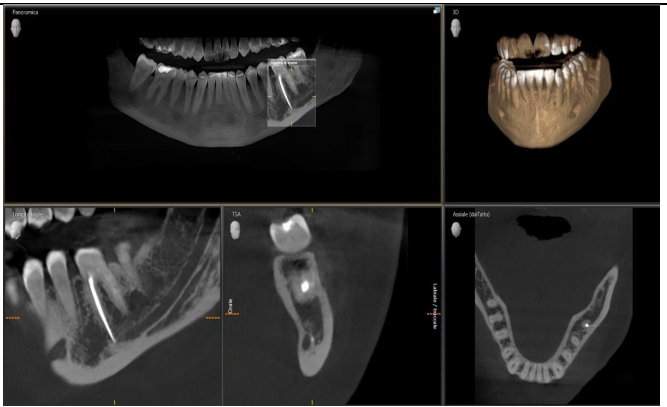

To assess the extent of the fracture and plan for removal, we obtained periapical radiographs and a cone-beam computed tomography (CBCT) scan. The imaging revealed the fractured NiTi instrument lodged deep within the canal system, complicating its retrieval due to its position approximately 8 mm beyond the apical foramen.

The successful removal of fractured endodontic instruments requires careful planning, appropriate imaging, and advanced techniques. In this case, the use of CBCT provided critical three-dimensional insights into the complex anatomy of the tooth, allowing for a more strategic approach to the retrieval process.

Figure 3

Figure 4